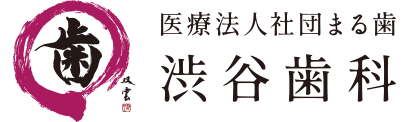

写真は、今までの入れ歯を全部持って来てくださった患者さまの入れ歯です。これだけ情報があると入れ歯治療のヒントが非常に得られます。